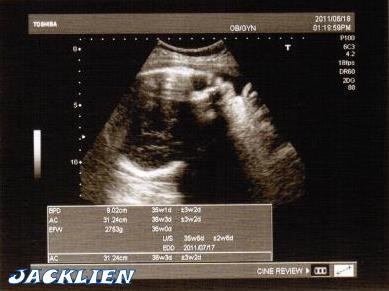

今天一開始醫生照平常習慣照了胎位,量了頭徑大小,聽了心跳…一切正常!

BPD 9.02cm (頭圍) 35w1d

AC 31.24cm (腹圍) 36w3d

EFW 2753g (體重) 36w0d,2011/07/17

哈~經過爸媽一週的催眠,兔兔真的很乖耶!

媽咪只多了0.2kg,兔兔只多了27g~不用擔心兔兔變巨嬰啦!

我每次去產檢的醫生都只會告知我頭圍目前多大 所以我都不知道我家的現在是多重幾g的說? 小連媽這是醫生給的超音波照片嗎? 因為跟我們這邊給的超音波照片不一樣,就只有寶寶的圖示基本的,只能說宜蘭的 機器比較簡單

金剛媽真愛開玩笑,當然是醫師給的啊,不然是我畫出來的哩,哈哈^^ 當初挑這個醫師就是他每一次都會幫媽咪拍照,也會印給媽咪做紀念! 傑克超愛看兔兔的寫真啦! 可能台北大醫院花比較多錢在買設備吧! 總之小金剛健康最重要啦~